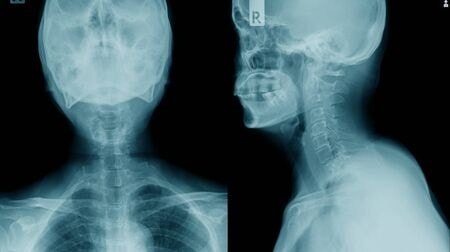

ESPONDILOSIS CERVICAL

En la zona cervical los síntomas producidos por la espondilosis vuelven a ser más frecuentes. La radiculopatía cervical, la mielopatía y la cervicalgia son los síntomas más frecuentes.

- Radiculopatía cervical: La radiculopatía es la irritación de una raíz nerviosa a nivel cervical, la mayoría de las ocasiones provocada porque la raíz está comprimida por una hernia discal o por el aumento del tamaño de las articulaciones cervicales que se produce como consecuencia de la espondilosis. La radiculopatía cervical se caracteriza por provocar un dolor que baja por el brazo, se trata de un dolor que no varía con los movimientos y que se asocia con pérdida de fuerza en el brazo, calambres y hormigueos.

- Mielopatía cervical: La mielopatía cervical es la compresión de la médula espinal a nivel del cuello. Cuando se comprime la médula espinal se afectan tanto las piernas como los brazos. Los síntomas más frecuentes son inestabilidad, dificultad para mover brazos y piernas, alteraciones en la sensibilidad e incluso alteraciones en los esfínteres en los casos más avanzados.